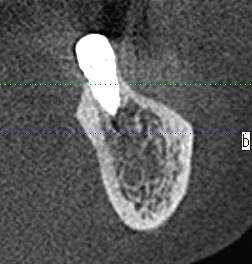

左下の7番部ではもっと埋入位置に制約が生じます

神経との距離も近くなります